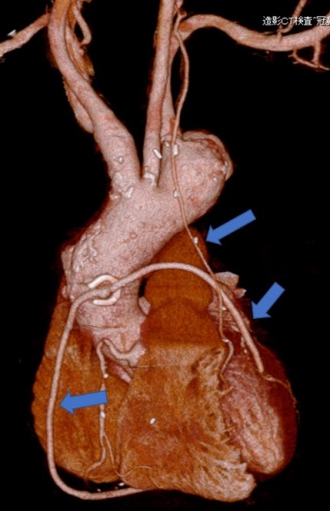

冠動脈バイパス術後。グラフとは3本とも開存している(矢印)。